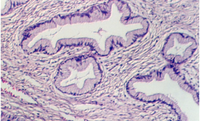

Slide 86 shows a uterus in the proliferative phase. The endometrium is illustrated in the photograph below. Note that the cells are low columnar to high columnar. The glands are relatively straight with a narrow lumina. Outside the glands is the highly cellular lamina propria. The following photos illustrate the proliferative phase with higher magnifications.

The uterus communicates with the outside world via a short canal called the cervix. The following photograph shows the uterus in the proliferative stage. The glands continue into the cervix in the left side of the photo.